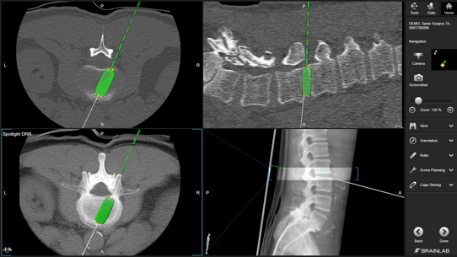

螺钉计划可在多视图布局中显示,迎合医生多视角对螺钉位置评估及观察的需求。(图11)

图11:术中导航